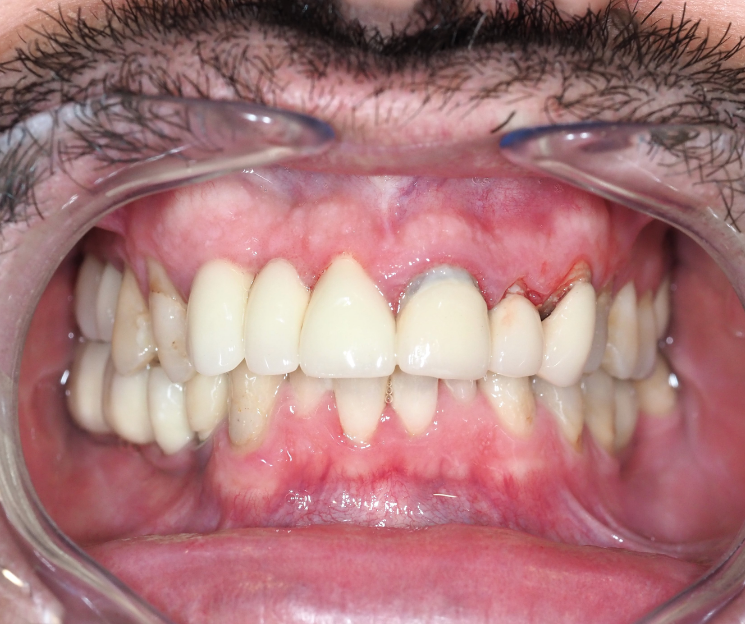

Paciente con infecciones de origen dental que comprometían severamente el hueso alveolar en la zona anterior superior. Se realizó la extracción de los dientes 21, 22 y 23, y se optó por una rehabilitación inmediata mediante implantes córticobasales.

Esta combinación permitió anclar los implantes en hueso cortical, que mantiene su estabilidad incluso en presencia de procesos infecciosos en el hueso alveolar. El resultado: rehabilitación funcional y estética el mismo día de la cirugía.

La rehabilitación postextracción de los dientes 21, 22 y 23 con implantes córticobasales no es un caso aislado. Es un ejemplo claro de cómo la odontología moderna puede resolver situaciones complejas de forma inmediata, estética y funcional.